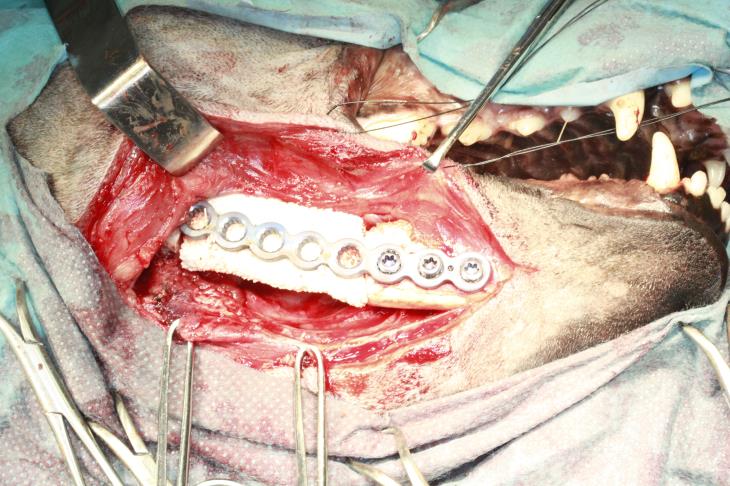

Preoperatively a 10mm cuffed tube was placed using a transmyelohyoid approach and secured with finger-trap sutures to allow unimpeded access to the oral cavity. The mandible was initially accessed by an extraoral approach and the margins of the resection marked. A ten hole 2.7mm PAX locking plate (Securos, UK) was then contoured to the mandible and fixed with two locking screws caudal to the proposed resection and three rostral. The plate was then removed and the surgical approach temporarily closed.

The mandible was then accessed via an intraoral approach and the tumour resected precisely according to the predetermined margins using a piezotome bone saw (Piezotome Solo – Acteon) and the oral wound was closed in two layers. The bone plate was then replaced via the extra-oral approach and secured in place with four 10mm and one 8mm locking screw. A template was made to fit the defect precisely and this was used to cut a compression resistant bone grafting matrix (Master Graft Strip, Medtronic, Hertfordshire, UK) to the correct size. The CRM (compression resistant matrix) was then infused with 1.32 mg of rh-BMP (TruScient – Zoetis) in 2.8ml of saline and placed in the defect and sutured circumferentially to the bone plate with poliglecaprone-25 to prevent movement of the graft. The extra-oral incision was then closed carefully in three layers